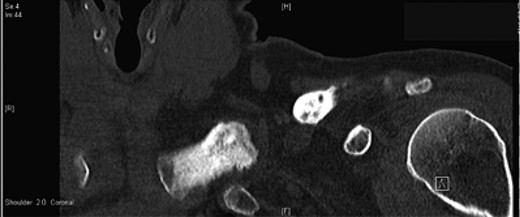

A 45-year-old woman presented with a 20-year history of a lump in the mid-third of the left clavicle, which had recently increased in size to 10 cm in diameter. Plain X-ray, computed tomography (CT) chest and clavicle, and bone scans were used to image the lesion (Figs 1–3). Radiology reported the lesion as a parosteal osteosarcoma, based on the CT appearance of tumour growing into the medulla of the mid-third of the clavicle; not usually a feature of an osteochondroma or an osteoma. Biopsies showed dense sclerotic bone, with no obvious malignant features. To confirm diagnosis complete excision of the tumour was needed, with a partial excision and scraping the lump off the surface deemed unsafe. The patient was informed that, following a total claviculectomy, a 30% functional loss (29.5% [8]) in her left shoulder power would be expected. Her active lifestyle meant this result was unacceptable, so she opted instead for excision of the tumour plus the adjacent clavicle, irradiation and reimplantation of the bone with internal fixation, despite this being relatively experimental. If successful, she would have virtually normal function. Although possible risks included infection or development of non-union, which would require further surgery or possible complete claviculectomy, it was deemed oncologically safe with a low risk of complications.

Preoperative CT scan, axial view showing the extent of the tumour.